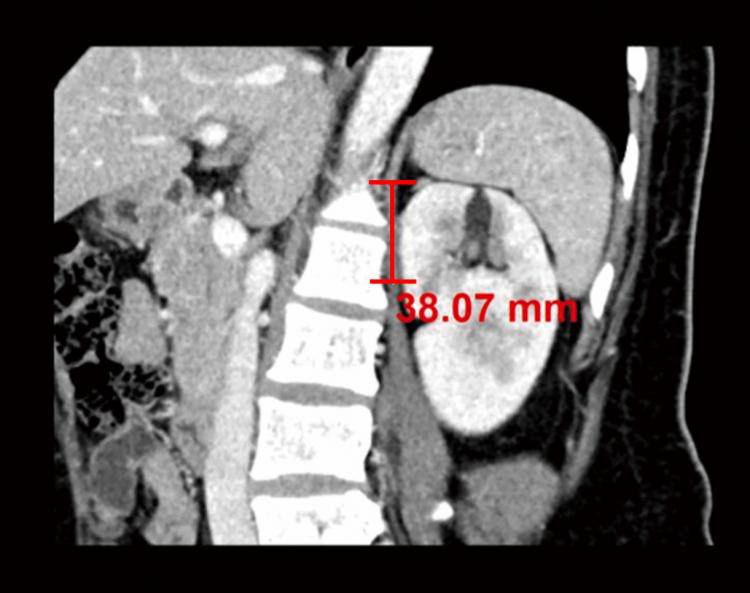

[Çѱ¹ÇàÁ¤´º½º - °æ±â¹æ¼Û±¹(±¹Àå:Á¤¿µ¸ð) ] ºÎ½ÅÁ¾¾çÀº Å©±âº¸´Ù À§Ä¡·Î ¼ö¼ú½Ã°£¡¤³­À̵µ ¿¹Ãø ÀÇÁ¤ºÎÀ»Áö´ëº´¿ø °©»ó¼±³»ºÐºñ¿Ü°ú ³ªÃæ½Ç, È«¼®ÁØ ±³¼ö ¿¬±¸ÆÀ ¡¯º¹°­°æ Èĺ¹¸· ºÎ½ÅÀýÁ¦¼ú¡¯ ¼ö¼ú½Ã°£ ¿¬Àå ¿¹ÃøÀÎÀÚ ¿¬±¸ ºÎ½ÅÁ¾¡¦